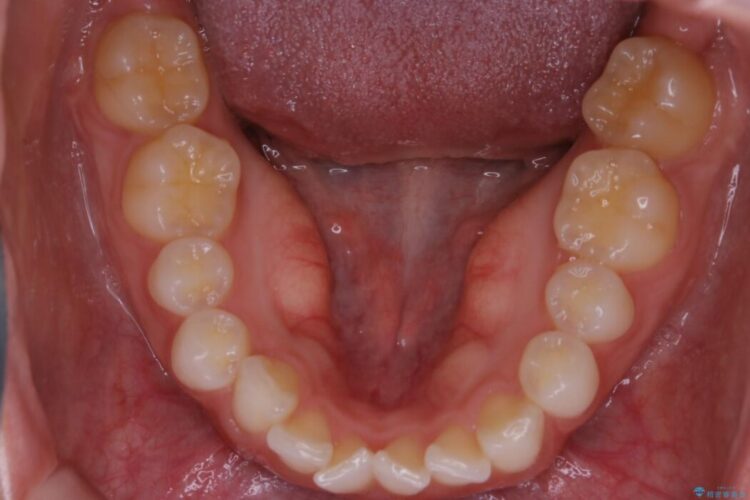

上下前歯のねじれなどで生じている歯列のガタつきをなおしたいとのことで来院されました。

精密検査をしたところ、奥歯に大きな問題がないため移動はほとんど必要がなく、また主訴であるガタつきの改善に必要なスペースも少量であったため、インビザラインのライトパッケージの治療をご提案しました。

半年という短期間でスピード治療が完了しました。